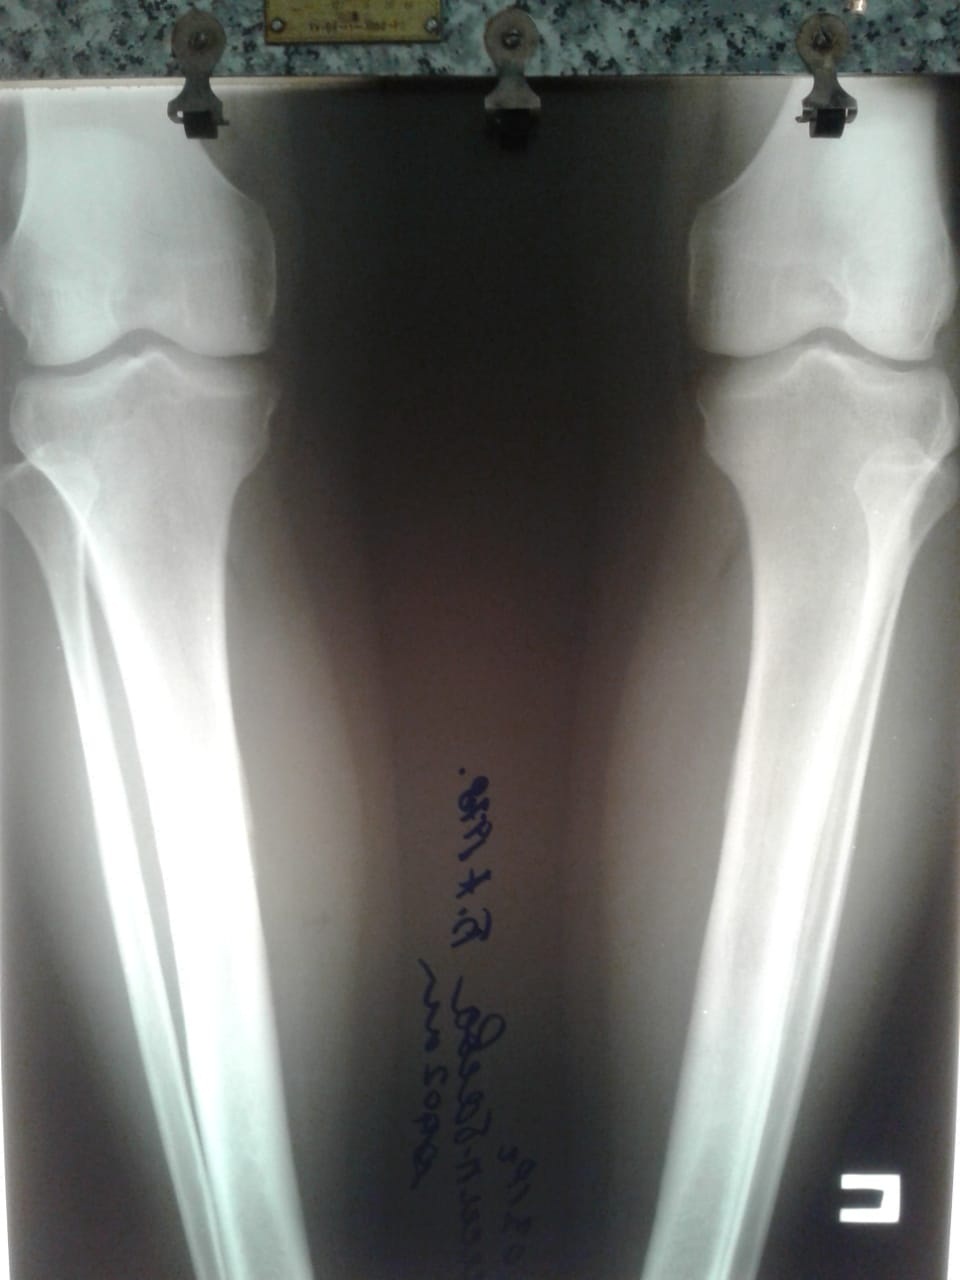

Ноги в сравнении, с чем приехали в Клинику